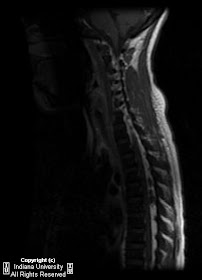

Findings

There are at least three non-enhancing T1 mildly hypo intense, T2 hypo intense masses in the posterior epidural space of the mid thoracic spinal canal causing mass effect on the adjacent spinal cord. There is also abnormal T1 and T2 hypo intensity of the vertebral body marrow.

Typical imaging appearance is of a lobular multi-segmental mass in the mid thoracic posterior epidural space that is T1 isointense and T2 hypo intense to the cord with variable enhancement.